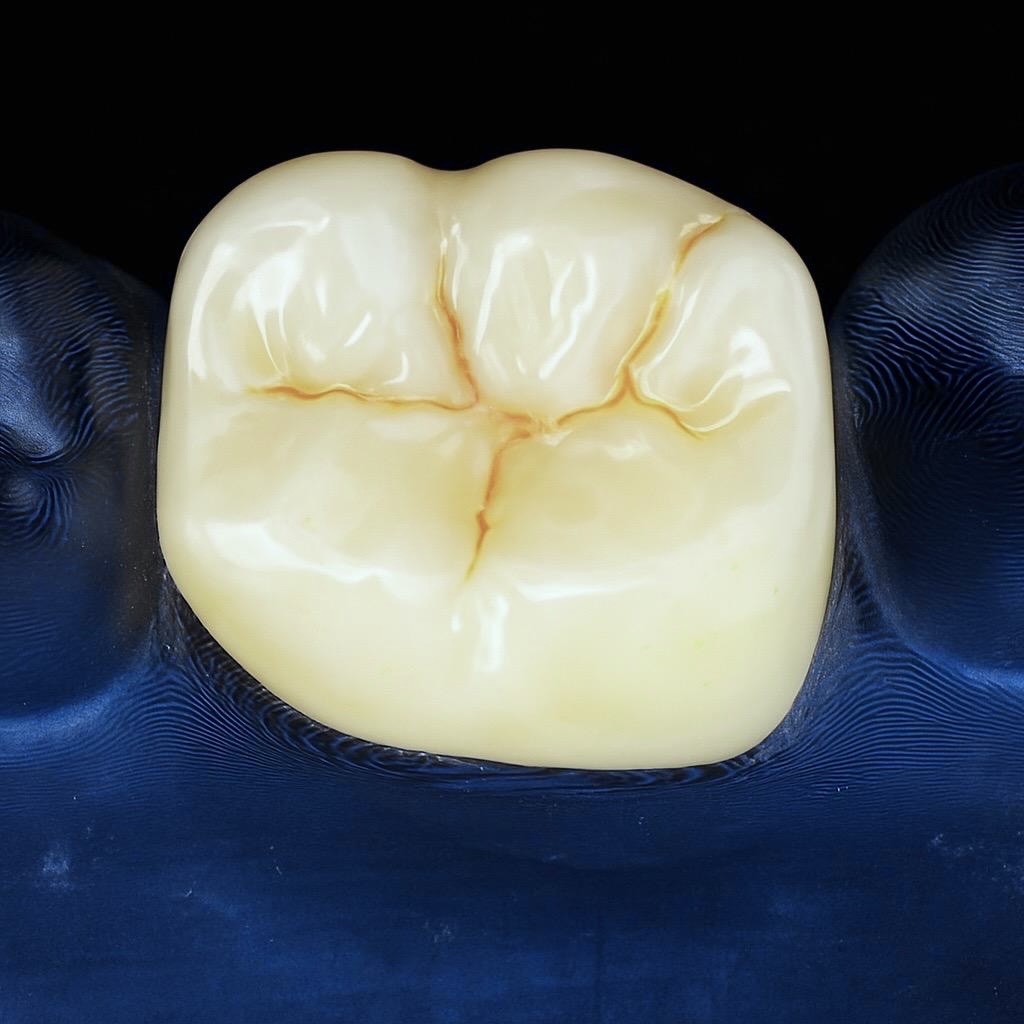

Follow-Up – 1 Year

- Radiographic healing observed – periapical lesion resolved.

- Surrounding bone density improved.

- Soft tissue response healthy and stable.

- Patient asymptomatic, full function restored.

- Restoration clinically intact with excellent marginal integrity.